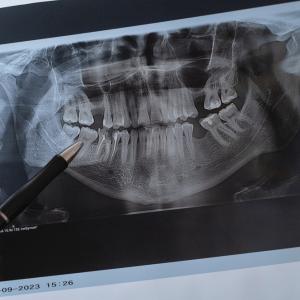

Японски учени са готови да започнат изпитания върху хора на лекарство, което може да възстановява зъби. Според местните медии, ако всичко е наред, клиничните тестове ще стартират през следващата година, а терапията за регенериране на зъби може да бъде готова за хората с беззъби усмивки още през 2030 г.

Когато става дума за първоначални изследвания, проучванията върху животни са особено подходящи. Сега обаче екипът иска да провери дали лечението действа добре при хора. Както съобщава японският вестник "Майничи", клиничните изпитвания ще започнат през юли 2024 г.